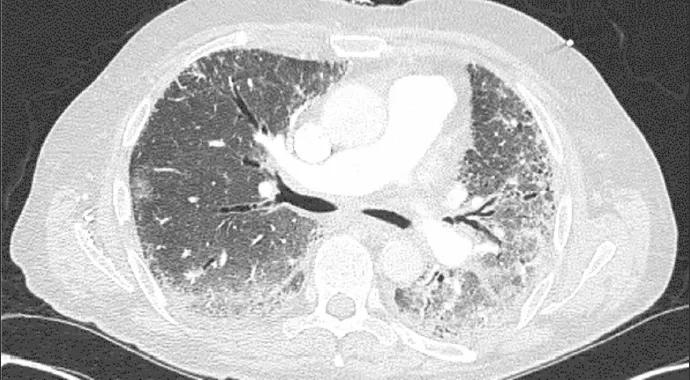

He had a positive ANA (5.7 OD ratio [normal, < 1.5]) and a positive Jo-1 antibody (antibody to histidyl transfer RNA synthetase). His creatine kinase was 700 U/L (normal, 30-220). EMG was consistent with a necrotizing myopathy. On pulmonary function testing, his forced vital capacity was 80 percent of predicted and his carbon monoxide diffusing capacity was 67 percent of predicted. Thoracic high-resolution CT scan revealed evidence of interstitial lung disease (ILD) characterized by bilateral patchy ground-glass opacities suggestive of active alveolitis, most extensive at the lung bases (Figure 1). A few months later, the skin of the tips and radial margins of his fingers started thickening and cracking, matching the classic description of “mechanic’s hands.”

Figure 1. Thoracic high-resolution CT scan in a 66-year-old man with interstitial lung disease and fibrosis associated with antisynthetase (anti-Jo-1) syndrome. Note the bilateral patchy ground-glass opacities suggestive of active alveolitis, most extensive at the lung bases, along with bilateral subpleural reticular infiltrates and interlobular septal thickening.